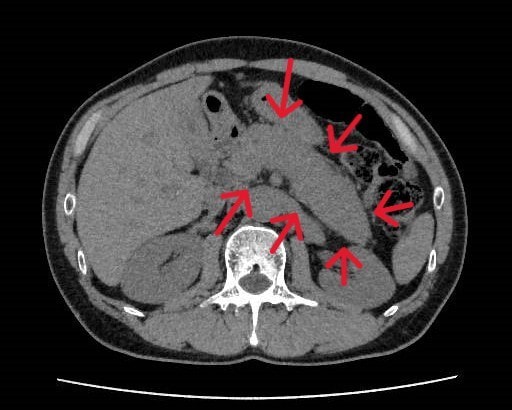

健診にて肝機能異常、皮膚黄染を認め、精査目的で当院消化器内科受診となった。今回実施されたdynamic CTではIgG4関連疾患を疑う所見が認められた。血液検査でもIgG4高値を示しており、IgG4関連硬化性胆管炎と自己免疫性膵炎が疑われ、ステロイドでの加療が開始された。

当該疾患の診断における造影CTの役割